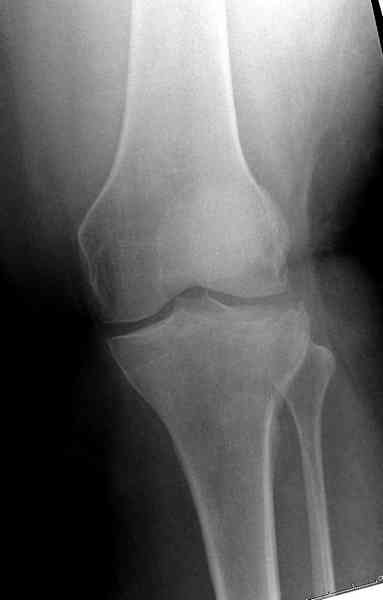

Здравствуйте, уважаемые коллеги!Подскажите, пожалуйста, какой выбрать доступ и способ фиксации при импрессионном переломе заднего отдела наружного мыщелка большеберцовой кости. Женщина 40 лет, травму получила 02.01.2008, катаясь на горных лыжах.Есть ли здесь необходимость использовать задний доступ, или можно справиться через наружный? Есть ли шансы сделать закрыто - под ЭОП через медиальное "окошко" поднять забойником суставную поврехность? Какой лучше использовать фиксатор?Спасибо.

Из медиального окна можно приподнять латеральную

импрессию. Фиксация тремя параллельными шурупами в

эпифизарной части над импрессией. Создается крыша,

которая предупредит коллапс. На образовавшуюся полость - костная пластика из аутокости или синтетический заменитель. Мы применяем Osteoset в 4-5 мм диаметре таблеточки или иньекционную форму Prodens.

Медиально, обычно на протовоположной

строне, делается окно в кортикальном слое, кривым забойником под рентгеном поднимается импрессия.

центральная импрессия, а при ипрессии с краевым переломом - после приподнимания импрессии опорная (Butress) пластина, как на снимке.